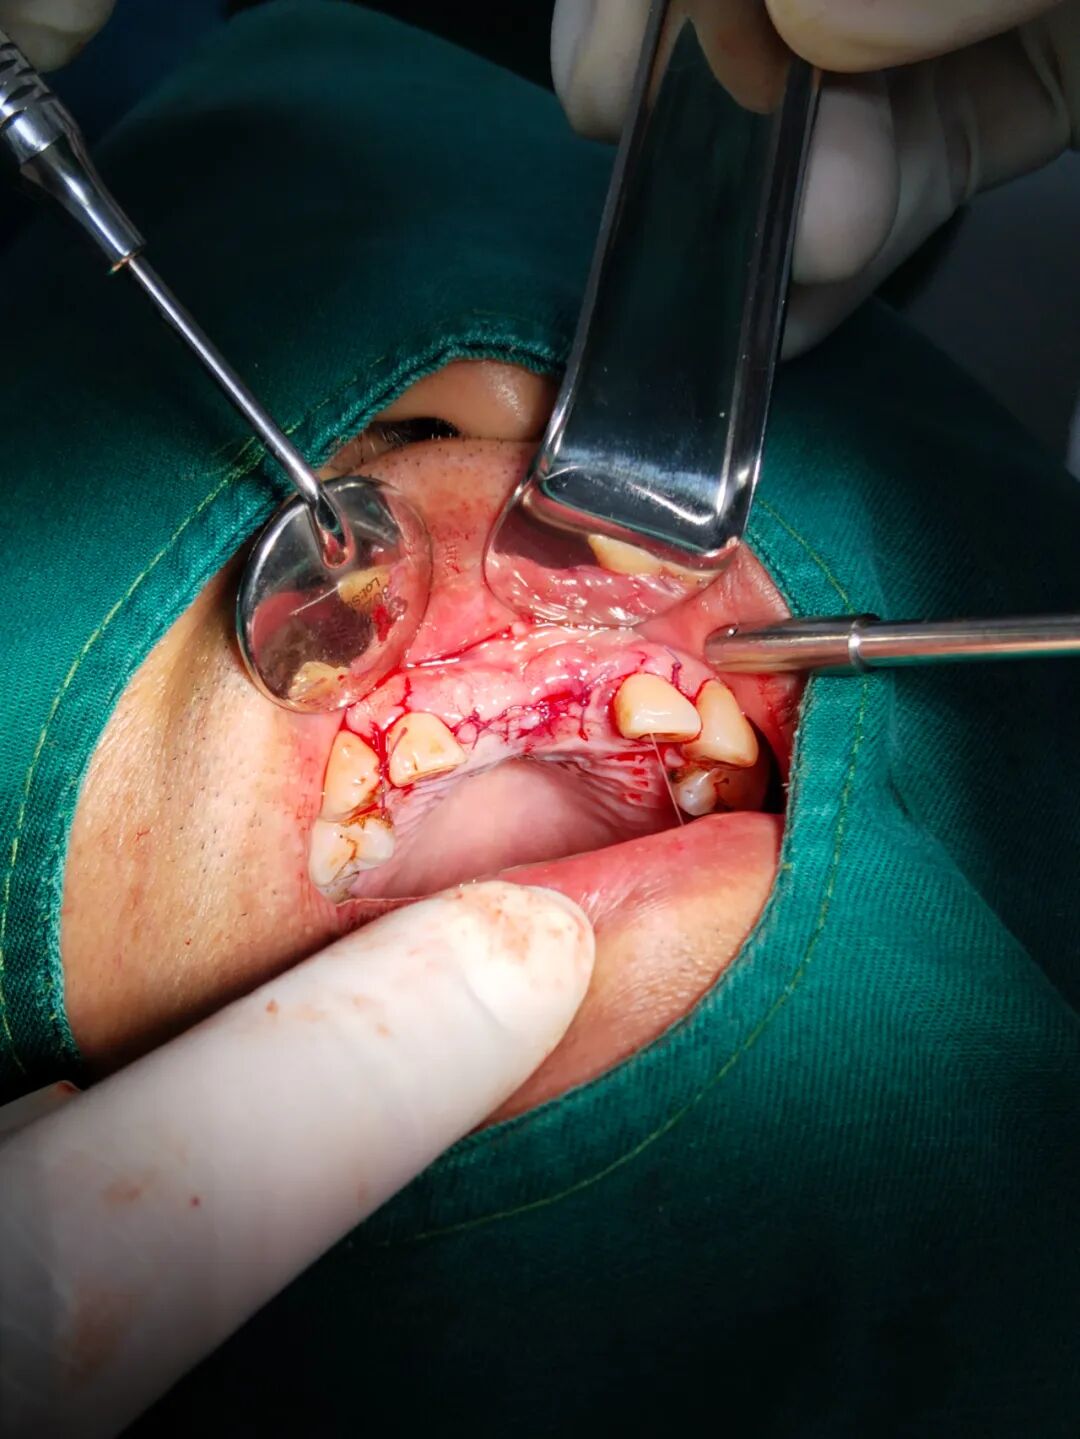

患者杨某,男,52岁,因上前牙缺失两年多,影响美观,就诊于我科决定行种植牙手术。术前CT检查,患者同意我科邰医生种植方案(数字化导板种植方案)。术中微创操作,术后无不良反应,整个疗程约一个小时,过程舒适、安全、精准,术后CT检查,种植体位置精准。